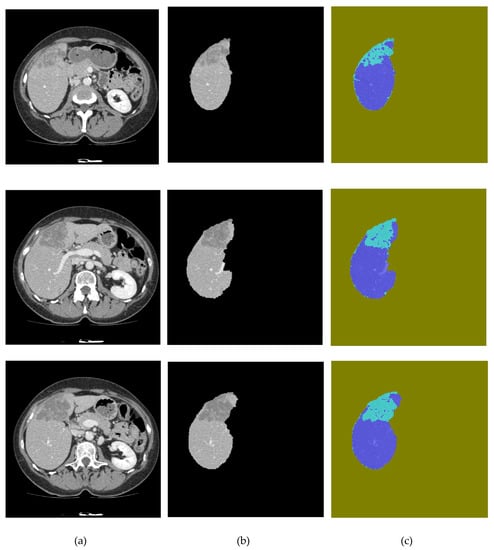

Figure 9.

Segmentation results: (a) original image, (b) liver segmentation using SegNet, and (c) UNet predictions of liver lesions.

The results demonstrate that the application of proposed SegNet-UNet-ABC algorithm over the Radiopaedia dataset achieved 0.96, 0.968, and 0.962 in terms of the Jaccard index, Dice index, and correlation coefficient, respectively, while it achieved 0.964, 0.97, and 0.958, respectively, for the three measures when it was tested on the LiTS dataset. It is obvious that the proposed method outperformed the NS-WS-FFCM method and the other method when each of them was applied to one of the datasets tested in this work. These results are due to the robustness of the SegNet and UNet in segmenting liver parenchyma and liver lesions from the CT images, respectively, which perform well in the case of absent clear edges, the definite shape of the liver parenchyma, in addition to the near connection between the liver tissue and the adjacent organs, as illustrated in the cases in Figure 9. In addition, the ABC bio-inspired optimization algorithm optimized the segmentation results of the liver parenchyma and liver lesions by selecting the best hyperparameters for SegNet and UNet which achieved the highest fitness in each step of segmentation.